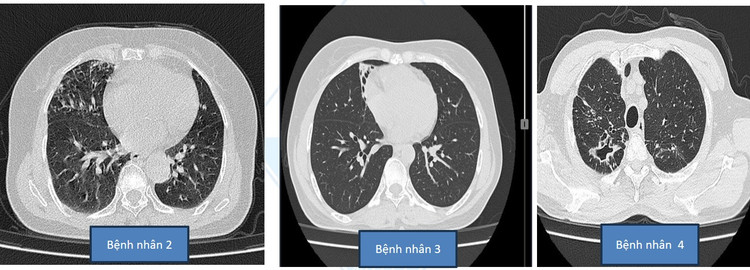

Tổn thương phổi do NTM của bệnh nhân tại Bệnh viện Đa khoa Medlatec Hà Nội.Tổn thương phổi do NTM của bệnh nhân tại Bệnh viện Đa khoa Medlatec Hà Nội.

Bệnh nhân N.V.T (70 tuổi, Tây Hồ, Hà Nội), vài tháng nay, có triệu chứng ho khạc đờm, sút cân, sốt về chiều. Đến khám hô hấp tại Bệnh viện Đa khoa Medlatec, bệnh nhân được chẩn đoán viêm phổi đặc hiệu: Hình ảnh tổn thương phổi hai bên kèm hạch trung thất hướng viêm, tuy nhiên chưa loại trừ lao. Vôi hóa động mạch vành hai bên. Vôi hoá cung động mạch chủ...

Để tìm nguyên nhân, PGS.TS.BS Hoàng Thị Phượng, nguyên Trưởng khoa Lao và Bệnh phổi, Viện Phổi Trung ương, chỉ định làm thêm xét nghiệm vi khuẩn lao là Acid Fast Bacillus (AFB). Kết quả thu được là âm tính. Xét nghiệm PCR, kết quả âm tính. Kết quả xét nghiệm vi khuẩn lao Xpert TB/R cũng âm tính.

Tuy nhiên, sau khi làm xét nghiệm nuôi cấy vi khuẩn lao trong môi trường Mgit, bệnh nhân dương tính với Nontuberculous Mycobacteria (NTM) - vi khuẩn không lao. Đây là loại vi khuẩn khó phát hiện, nếu để lâu, người mắc phải mất nhiều thời gian điều trị, bệnh tình kéo dài, gây thiệt hại về sức khỏe và kinh tế.

Với hơn 30 năm kinh nghiệm khám lâm sàng, gần 20 năm nghiên cứu về vi khuẩn không lao NTM, PGS.TS.BS Hoàng Thị Phượng đã tìm ra căn bệnh, đưa phác đồ điều trị hiệu quả cho bệnh nhân, rút ngắn quá trình điều trị.